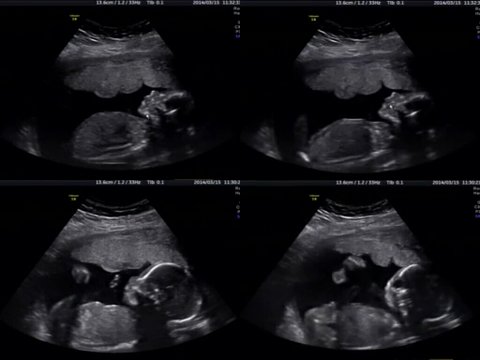

구미 거주중인 21주 된 아들 품고있는 21살 어리다면 어린 엄마입니다.